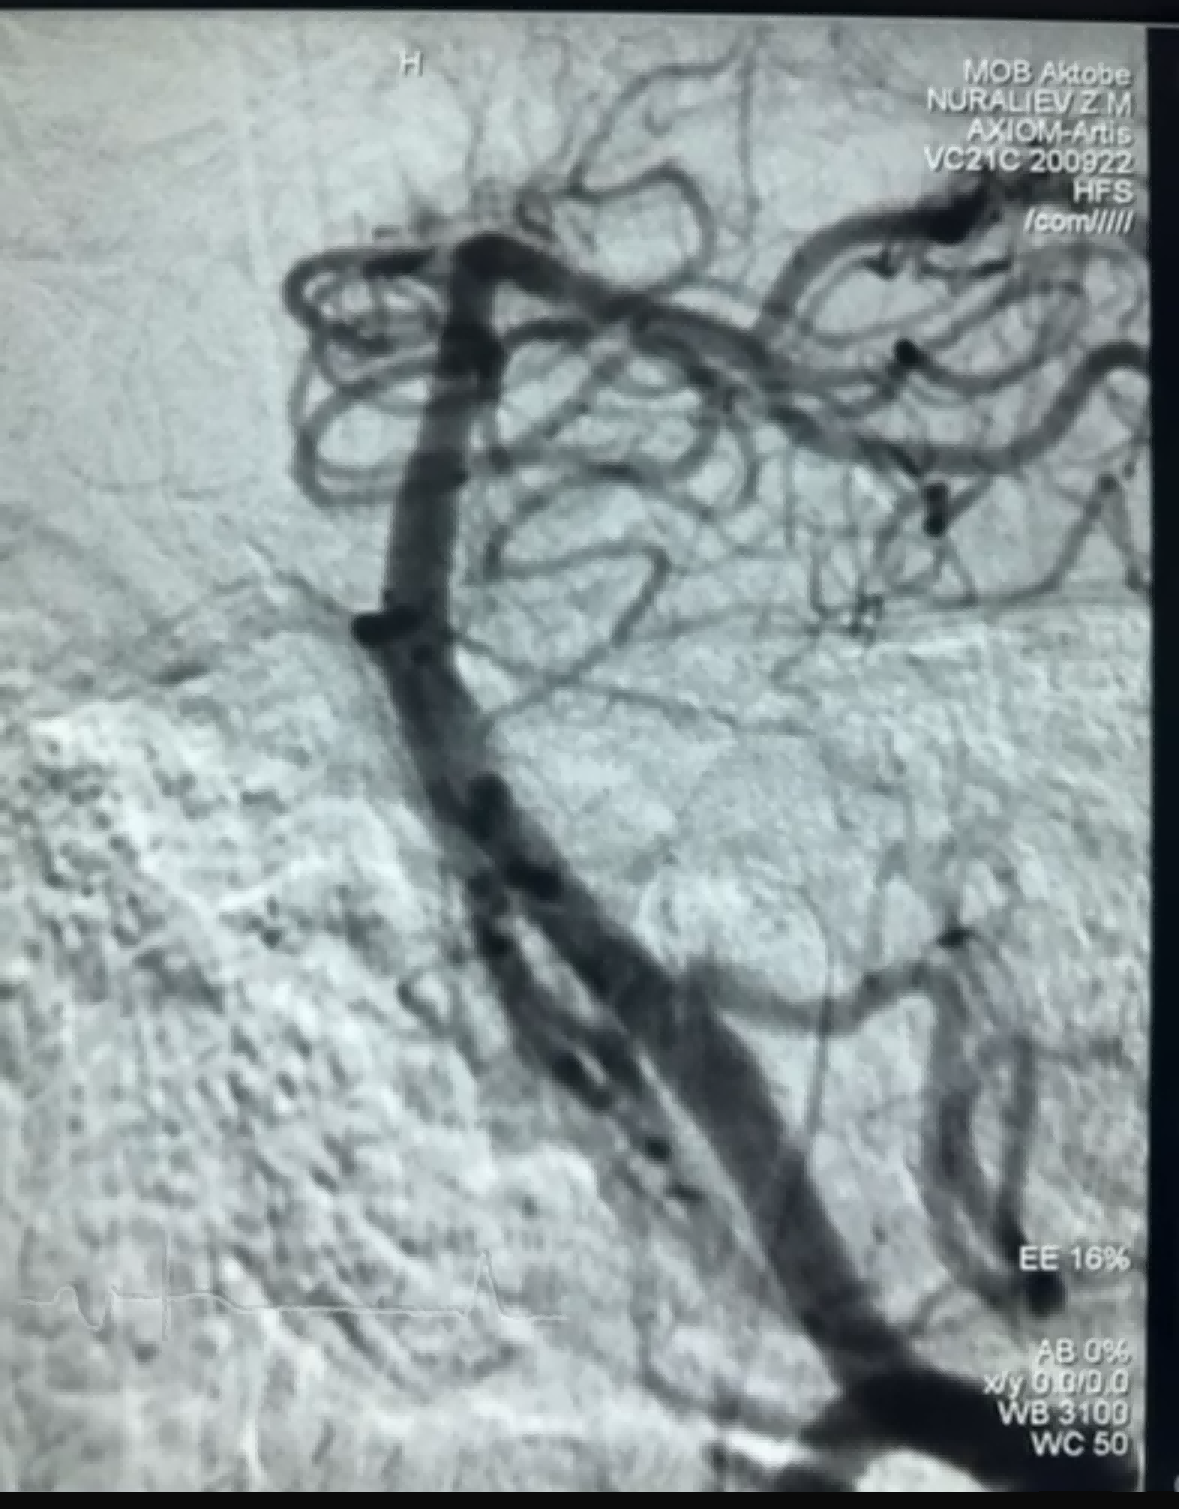

Pred kratkim je bil uspešen primer trombektomije z uporabo naprave Dredger Stent Retriever podjetja NeuroSafe Medical Co., Ltd. Dredger Stent Retriever ima neinvazivno mehko konico, ki močno zmanjša tveganje za poškodbe intime, in ima edinstveno luknjo posebne oblike. zasnova, ki zajame krvne strdke predvsem z vpenjanjem sprememb vrzeli.